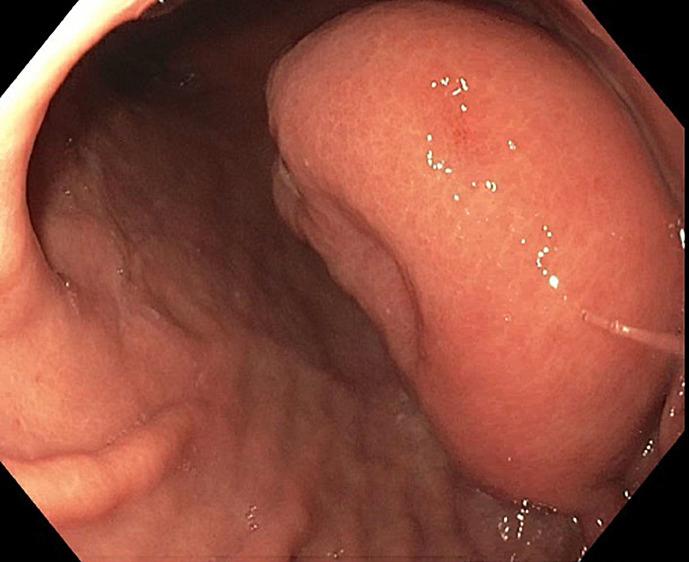

The purpose of this case series was to review a rare subset of tumors known as gastric lipomas, which are typically found incidentally. The motivation for this study arose from the identification of 2 cases within our institution in a short period.

CASE PRESENTATION

The study involved a review of the diagnosis and management of 2 patients presenting with gastric lipomas at our institution after symptoms of gastrointestinal bleeding. With the advent of new radiologic investigations such as computed tomography and magnetic resonance imaging and advances in endoscopy, there are new approaches to identifying and managing these tumors. On further evaluation of the literature, we found that despite the availability of minimally invasive endoscopic techniques such as mucosal resection and submucosal dissection in the setting of large tumors, most patients tend to have to resort to surgical management.

本病例系列的目的是回顾一类罕见的肿瘤,即胃脂肪瘤,这类肿瘤通常是偶然发现的。本研究的动机源于我们机构在短时间内确诊的2例病例。

病例介绍

本研究回顾了我院2例出现胃肠道出血症状后被诊断为胃脂肪瘤的患者的诊断和治疗情况。随着计算机断层扫描和磁共振成像等新的放射学检查方法的出现以及内镜技术的进步,出现了识别和处理这些肿瘤的新方法。在进一步查阅文献时,我们发现,尽管对于较大的肿瘤可以采用黏膜切除和黏膜下剥离等微创内镜技术,但大多数患者往往仍需采取手术治疗。